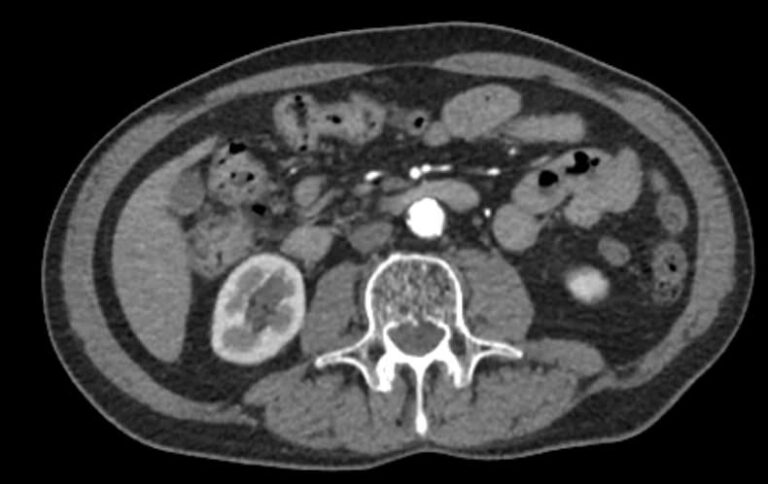

Основные показания для проведения КТ брюшного отдела аорты и артерий нижних конечностей могут включать:

• Аневризмы: оценка и диагностика аневризм брюшной аорты.

• Стенозы и окклюзии: выявление и оценка степени сужения или блокировки артерий.

• Тромбозы: обнаружение тромбов и оценка их размера и локализации.

• Атеросклероз: определение степени и распространенности атеросклеротических изменений.